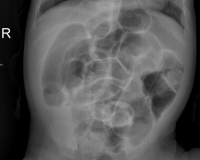

• Рентгенография брюшной полости. Патогномоничным признаком кишечной непроходимости являются чаши Клойбера, которые представляют собой растянутые петли кишечника, наполненные калом и газами. На рентгенограмме заметен симптом каймы (вздутые складки слизистой оболочки).